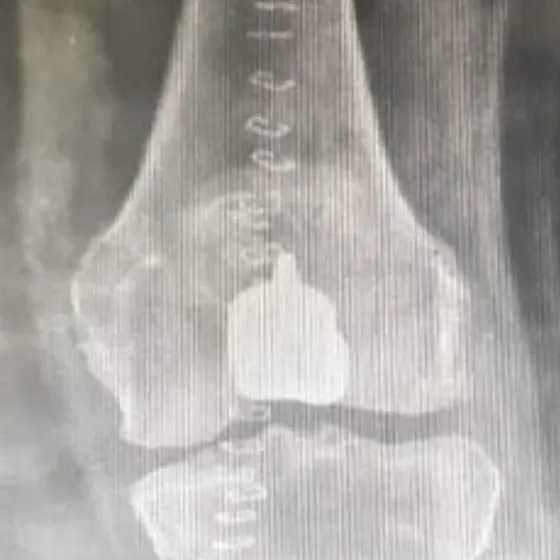

Episurf trochlear patellar replacement

Advance Hospitals, Ahmedabad Becomes the First in the Region to Perform Patient-Specific Patello-Femoral Replacement Using the Episurf Technique

Ahmedabad, July 2025 — In a groundbreaking achievement, Advance Hospitals, Ahmedabad has become the first center in the region to perform patient-specific patello-femoral replacement using the Episurf technique, a revolutionary approach in joint preservation and early knee arthritis management.

The surgery was successfully performed by Dr. Prathmesh Jain, a leading arthroscopy and joint preservation surgeon and Director of Advance Hospitals. Known for his innovations in cartilage and ligament surgery, Dr. Jain has once again positioned the hospital at the forefront of orthopedic excellence.

The Episurf technology involves custom-made implants designed for each patient based on 3D MRI analysis, ensuring precision fit, minimal bone loss, and faster recovery. This technique is particularly beneficial for younger patients with isolated patellar or trochlear cartilage damage who are not ideal candidates for total knee replacement.

“This is a game-changer for young patients with early patello-femoral arthritis or cartilage injuries. With Episurf, we are able to treat the damaged area precisely without compromising healthy bone and joint structure,” said Dr. Prathmesh Jain.

Advance Hospitals continues to lead in innovation by offering world-class surgical solutions for cartilage repair, meniscus preservation, ACL reconstruction, and now, customized knee resurfacing with Episurf—providing patients a new lease on active life.